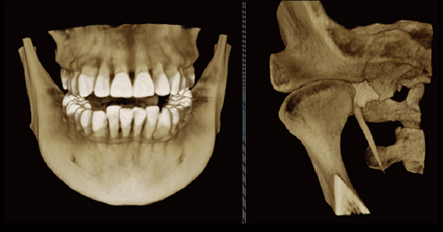

朗视Smart3D-X四合一智能口腔CBCT,创新地整合了CT、全景、头颅和口内摄影(牙片)四种影像的拍摄功能,配套软件同时支持四种影像的查看和处理。

CT摄影

360°完整扫描,800帧超清影像,配合高性能CT算法,呈现细腻影像

C型臂可实现对患者头颅360°的完整扫描,最小体素尺寸0.05mm,分辨率可达2.2lp/mm,800帧超清拍摄,<60s重建时间,配合高性能算法精细重建,更适合牙体牙髓疾病的诊断。

朗视配套SmartV软件还可将采集到的数据进行多平面组合重建,不但可以同时观察到轴向面、冠状面和矢状面图像,而且可以在任意位置进行断层切面,同时获得颊舌向切片和远近中切片,方便医生诊疗。